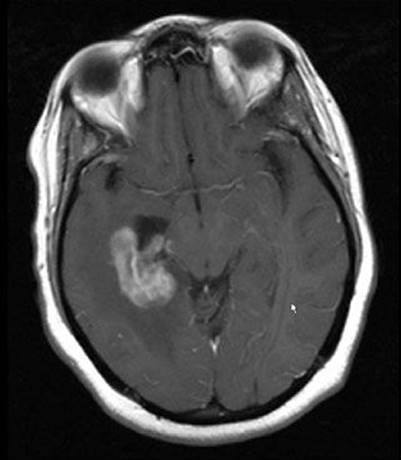

FIGURE 34.1. Example of periventricular location of human immunodeficiency virus–associated primary central nervous system lymphoma.

Patterns of Disease

In most patients who have HIV-associated PCNSL, the diagnosis is suggested by the onset of headaches or a change in mental status.36,37 Unfortunately, PCNSL can be clinically and radiographically indistinguishable from other pathologic processes in HIV-infected patients. Neurocognitive dysfunction in HIV-infected patients is associated with a long differential diagnosis, including PCNSL, toxoplasmosis, herpetic infections, cryptococcus, progressive multifocal leukoencephalopathy, neuroimmune reconstitution inflammatory syndrome (IRIS), and HIV-associated dementia, leukoencephalopathy, and demyelination. In general, the typical radiographic findings of PCNSL are that of multiple contrast-enhancing lesions, often, but not exclusively, in a periventricular location (Fig. 34.1).